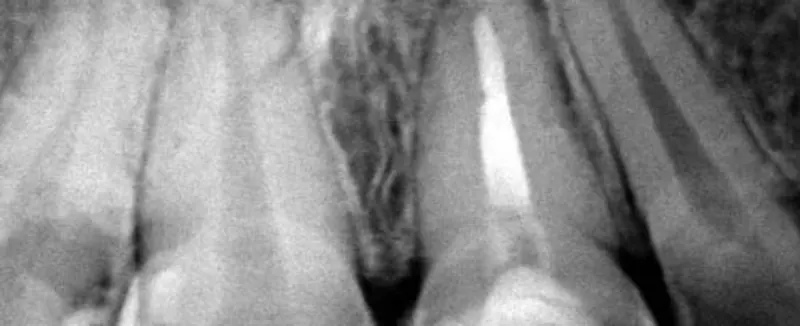

Extracción de terceros molares, colocación de implantes y cirugías con enfoque conservador.